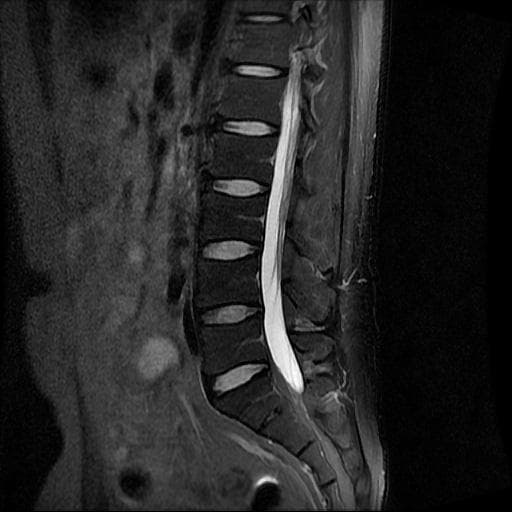

이번에 허리 MRI찍었는데

상태 어떤지 고견 여쭙습니다.

큰 이상이나 문제점은 없어 보이는 것으로 생각되는데요, 허리통증이 지속되는 경우에는 반드시 디스크 질환에 의한것은 아닐 수 있습니다.

우선 사진만으론 정확히 판단 할 수 없기에 전문의에 소견을 들어보시길 추천드립니다.

현재로썬 디스크 상태는 심하지않는것으로 확인이 됩니다.

MRI 영상 커트로 판독을 할 수는 없습니다.

전체 커트를 올리시던가 아시면 판독지를 올려주시면 도움을 드릴 수 있습니다.